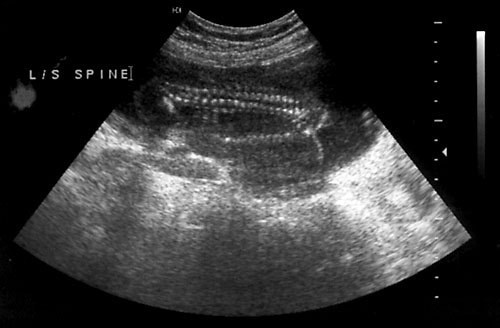

Normal cervical spine at 18 weeks (1). Another normal sagittal view of cervical spine seen in third trimester with folds of fat seen (2). Normal thoracic spine at 18 weeks (3). Normal sagittal view of lumbosacral spine at 18 weeks (4). Normal transverse view of lumbosacral spine at 18 weeks (5). - Extremities (hands/feet)